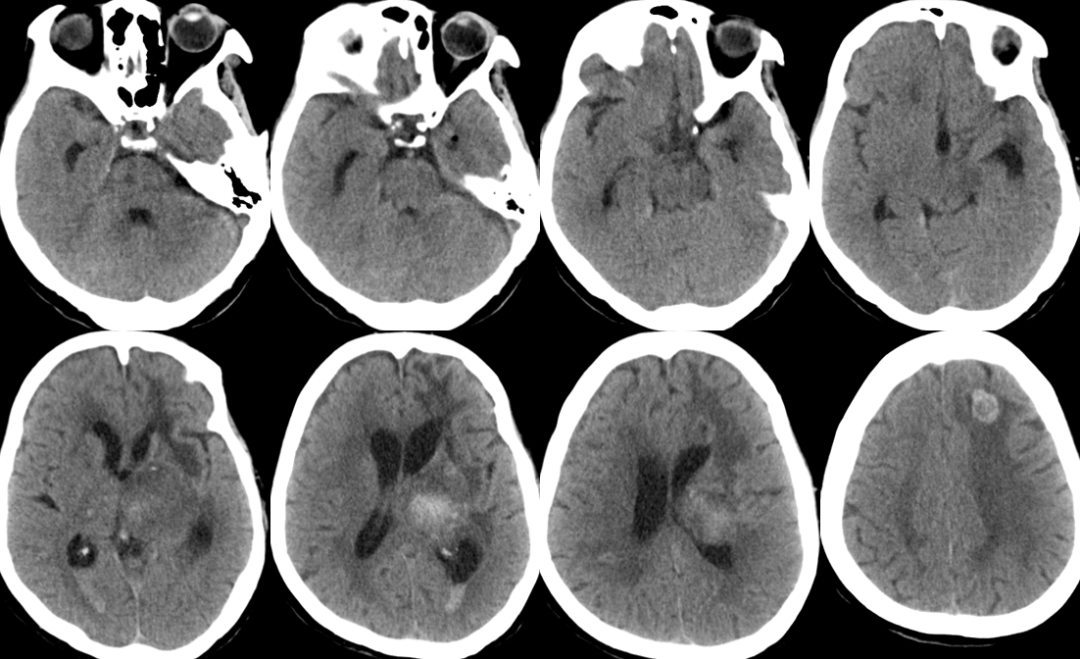

2014-11-19 CT

2014-11-20 CT

再出血?

脑水肿?

脑积水?

腰大池过度引流?(非高颅压脑疝)

肺炎?

2014-11-24 CT

气颅、轻度脑积水,加强脱水,必要时用激素